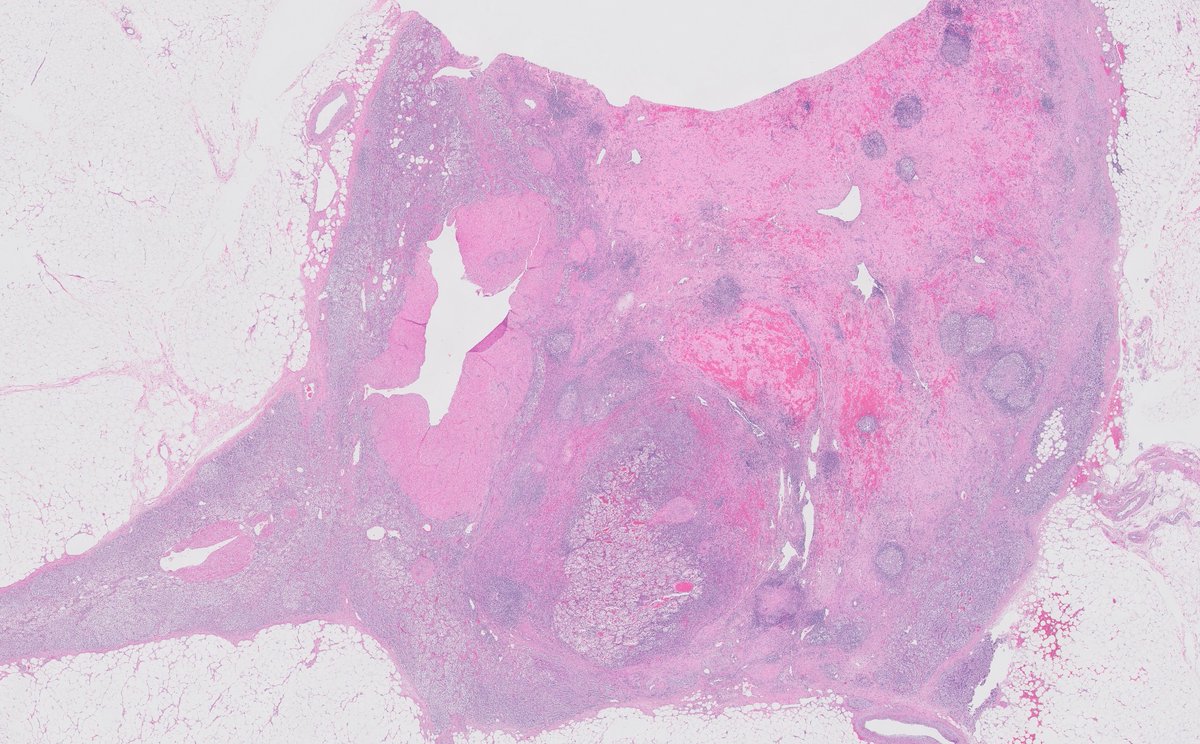

@GladellPaner

Uniquely intricate morphological pattern in #renal tumor! Catchy for #OnePicDx! 🔍 What is your diagnosis on this #nephrectomy #GUPath tweeps? Answer in comment👇👇👇